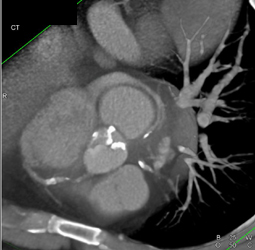

Calcified Bicuspid Valve